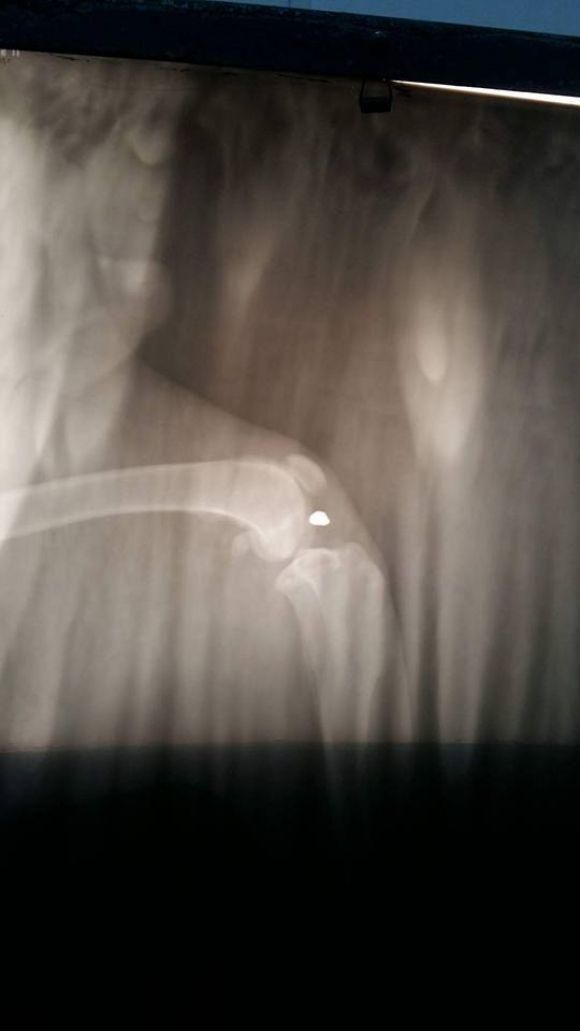

На подвір'ї 23 лютого хтось стріляв в нашого Роккі, нажаль ветеринар не зміг дістати кулю, завтра треба знову робити рентген і шукати кулю. Про це у "Фейсбуці" написала Oksana Bodnaruk.